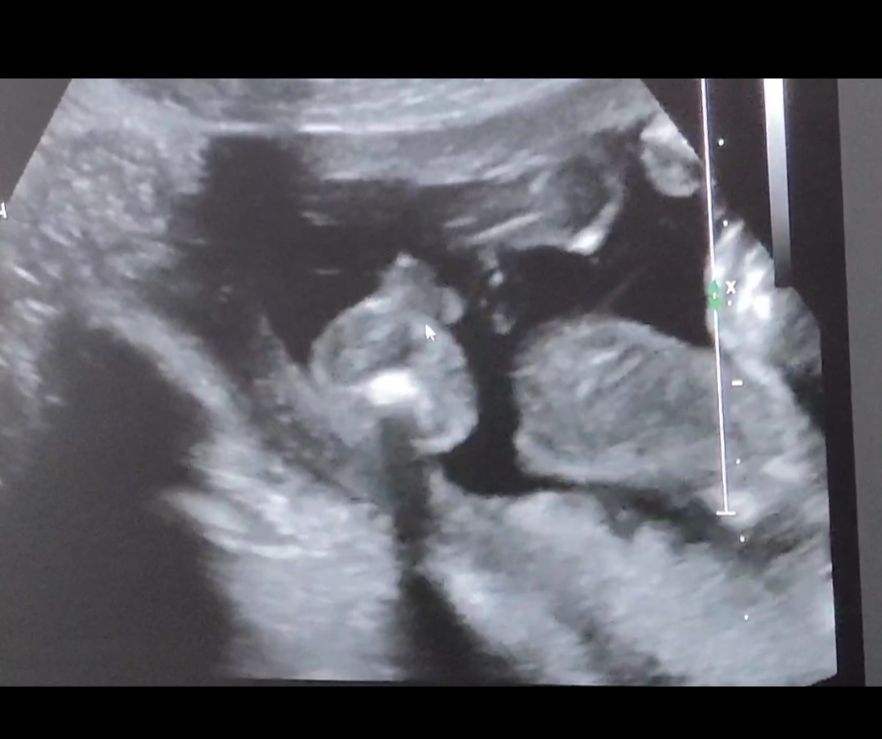

Пришли к УЗИсту узнать пол до скрининга, который сказал, что у меня замершая на 90 проц🤣УЗИст может узнал меня, сказал бесплатно скажет. А мы теперь ему до конца не доверяем. Мышкой показывает мошонку, а мы не совсем понимаем, так как смотрели минуту🤣 как будто справа ноги согнутые и булки понятно

Я, когда видео идёт, видно, что смотрим снизу на булки, ноги согнутые, а что за большой круг не понимаем

Похоже на мальчика, да. За точность не отвечаю 🤭 Там же внизу попа, указатель мышки на мошонке?